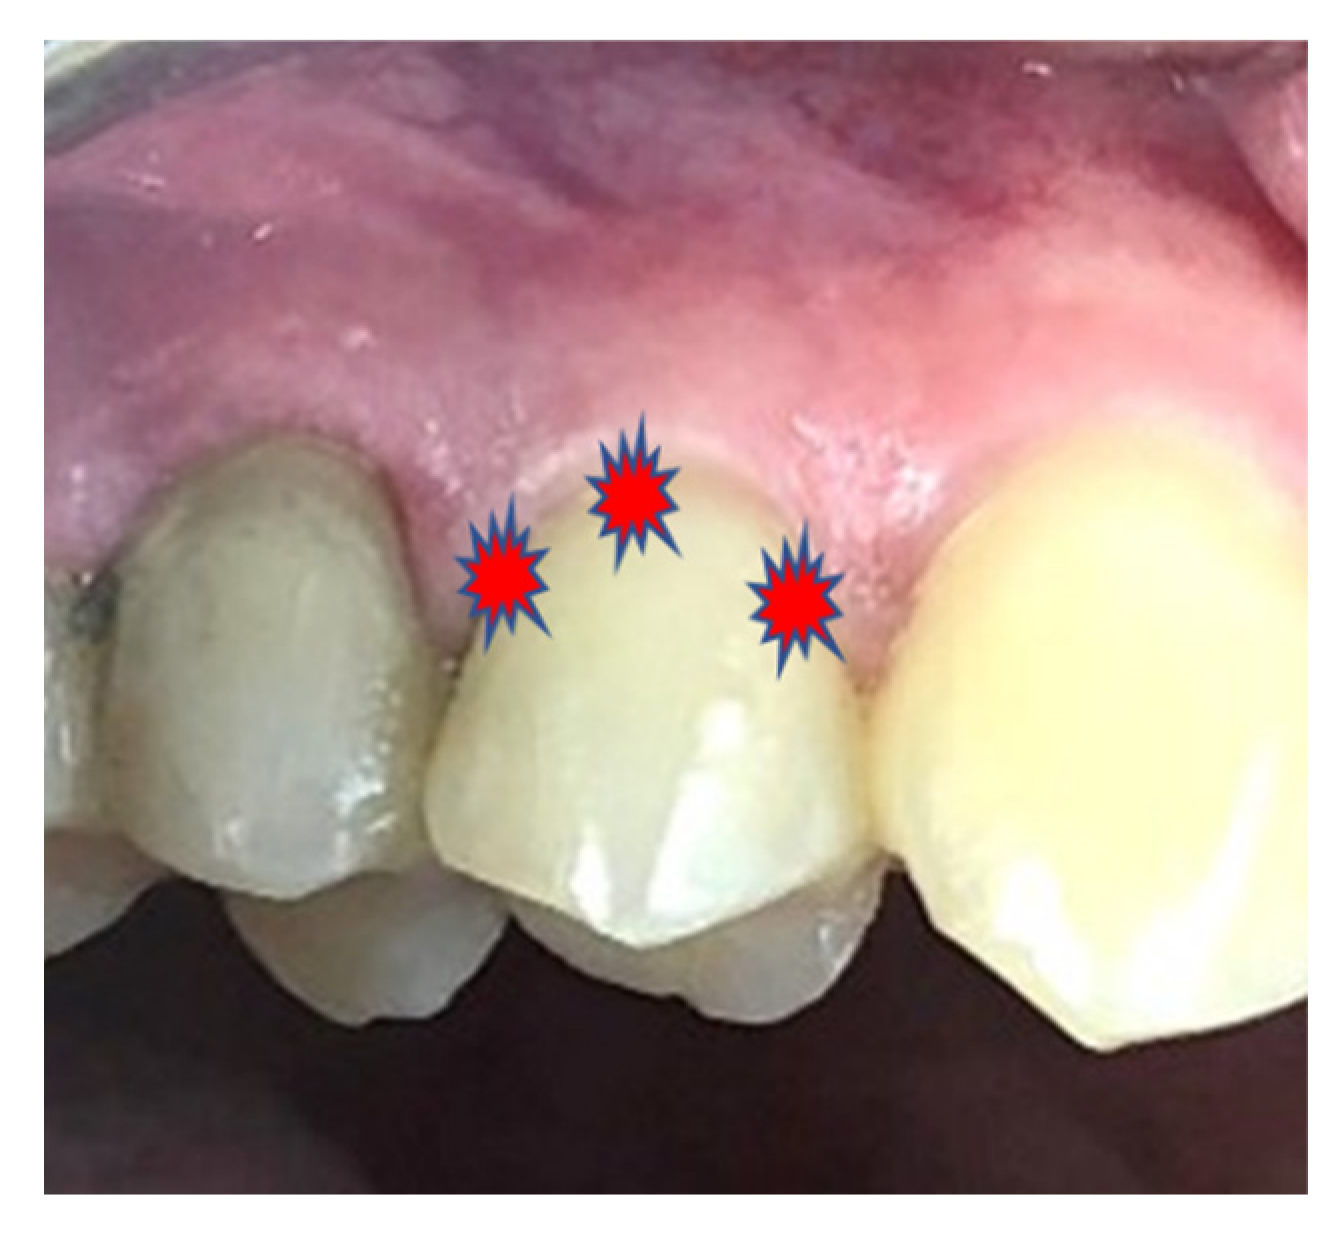

2.2. Inclusion and Exclusion Criteria

2.3. Assessment and Follow-Up